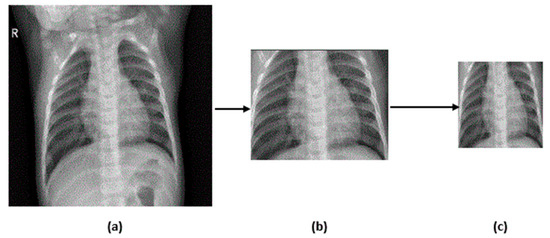

4.2. Image Processing